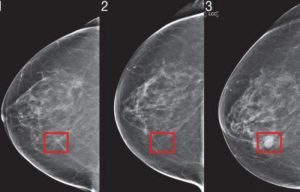

AI algoritmi, trenirani na ogromnim količinama podataka iz mamograma, sada imaju sposobnost uočavanja suptilnih abnormalnosti koje ljudskom oku ostaju nevidljive. Ovi sistemi ne samo da pomažu u preciznoj dijagnozi već mogu identificirati promjene koje ukazuju na početne faze raka, često mnogo prije nego što konvencionalne metode otkriju bolest.

Zahvaljujući svojoj nevjerojatnoj sposobnosti analize i prepoznavanja uzoraka u podacima, umjetna inteligencija ne samo da može uočiti postojeće promjene u tkivu, već i predvidjeti mogućnost razvoja bolesti u budućnosti.

Na temelju tih predviđanja, AI nudi mogućnost ranog otkrivanja, što omogućava promptno liječenje i potencijalno spašavanje života. Iako mnogi stručnjaci već ističu visoku točnost ovih tehnologija, AI sistemi također smanjuju učestalost lažno pozitivnih i negativnih nalaza, što čini dijagnozu još pouzdanijom.